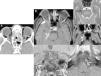

Maintaining the same approach as in the first part, focusing on the clinical presentations in the emergency department rather than on the anatomic regions affected, we will study the entities that present with two patterns: those that present with a combination of cervical numbness, dysphagia, and dyspnoea and those that present with acute sensory deficits. In the latter group, we will specifically focus on visual deficits, because this is the most common symptom that calls for urgent imaging studies.